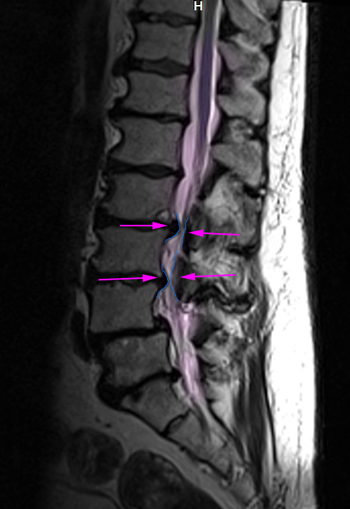

LumbarLaminectomy

Στένωση οσφυϊκού σπονδυλικού σωλήνα (φούξια). Τα όρια της προγραμματισμένης πεταλεκτομής αναδεικνύονται με πράσινο και συμπεριλαμβάνουν το πέταλο και μέρος των μικρών αρθρώσεων (μπλέ).